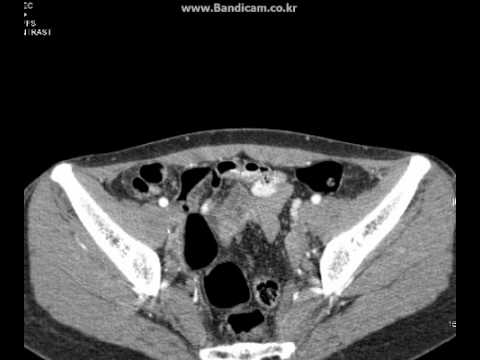

HỘI CHỨNG FITZ-HUGH-CURTIS. Thread starter BOT2; Start date Nov 26, 2016; B. BOT2 Administrator. Staff member. Nov 26, 2016 #1 Nữ 36 tuổi. Đau toàn bụng ngày thứ nhất, không phản ứng thành bụng. Đi cầ